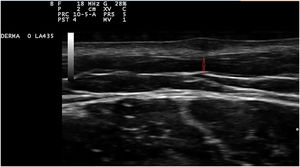

Exploration revealed the presence of small, elastic nodules and papules with poorly defined borders, covered by slightly hyperpigmented skin and fibroelastic in consistency (Fig. 1). Some were painful when palpated. Ultrasound examination of the nodules in her left arm and thigh revealed highly vascularised hypoechoic lesions (Fig. 2).